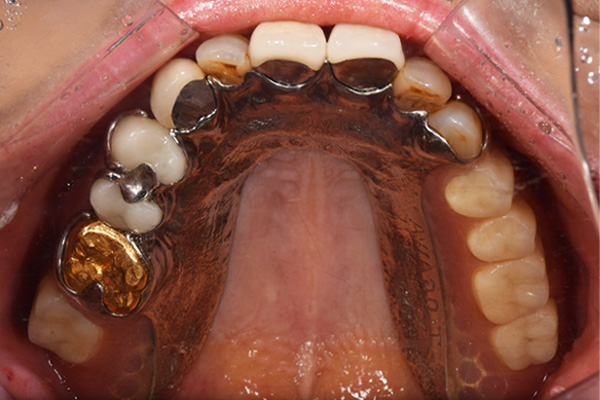

ケース4

(アタッチメントを用いた部分入れ歯)

右上のインプラント周囲炎で、その部分が痛いという患者様でした。 また奥歯で噛むことが難しかったため、前歯を使用することが多くなり、 前歯が前よりも前に出てきていることも気になっていらっしゃいました。

インプラント部以外にも歯周病が進行していましたので、歯周病の治療を行いました。 残念ながらインプラントと、1本の歯が残せなかったため抜歯を行いました。 その後、前歯の出っ張りを修正することと入れ歯の安定を図るため、残っている歯を全てかぶせ物にしていくことになりました。 写真中央は抜歯後に入れた治療用の入れ歯になります。 抜歯後歯ぐきが安定しましたら、入れ歯とかぶせ物の型取りを行いました。

噛み合わせチェックでしっかり奥歯で噛めるようにし、 歯を並べます。 その後、それに合わせて前歯を作っていきます。

最終的な入れ歯用の型取りをします。 シリコンで精密に型取りができました。

こちらが完成したかぶせ物と入れ歯です。かぶせ物にはアタッチメントをつけて金属のバネが見えない構造になっています。 入れ歯自体も金属を使用して、極力違和感がでないように、薄く作成しました。

お口の中に入れた状態です。 非常に見た目もよい出来となりました。 バネがみえないと見栄えが全然ちがいます。

年齢 70代・女性

主訴 奥歯のインプラントが痛い。

前歯がでてきた。

治療期間 6ヶ月

治療費 .メタルボンドクラウン7本:770,000円

.アタッチメント2個:220,000円

.義歯:550,000円

治療方針 ゆれてきたインプラントを抜去した後、歯周病の治療と、予後不良の歯を抜歯して、義歯を作成します。

抜歯後は治療用の入れ歯を作成し、ものが噛める様にします。

また前歯は、被せものをすることにしました。

治療内容 右上のボーンアンカードブリッジ(インプラントのブリッジ)部分がインプラント周囲炎になり、ぐらぐら揺れてきました。

そのため、インプラントを抜去した後、歯周病の治療と、予後不良の歯を抜歯して、義歯を作成していきました。

見た目が入れ歯とわからない様に針金のない、アタッチメントを使用した入れ歯を作成することにしました。

抜歯後は奥歯でものが噛める様に治療用の入れ歯を作成しました。

また前歯はフレアアウト(奥歯で噛めなくて前歯で噛む様になって、前歯が前に出てくる現象)していたため、患者さんの希望でかぶせ物をすることにしました。

特記事項 歯やインプラントを抜いた後は、2〜3ヶ月歯ぐきの回復を待ってから入れ歯を作るため、待機期間があります。その間、治療用の入れ歯を調整しながら使います。かぶせものをした後は歯がしみたり、場合によっては神経を抜く処置が必要になることもあります。